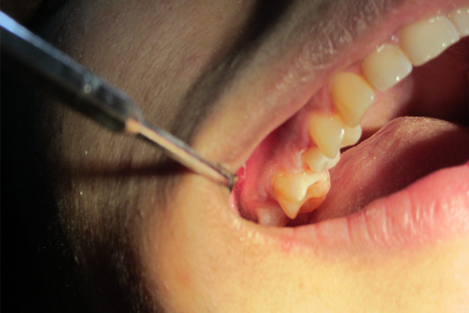

Dental Dam Isolation